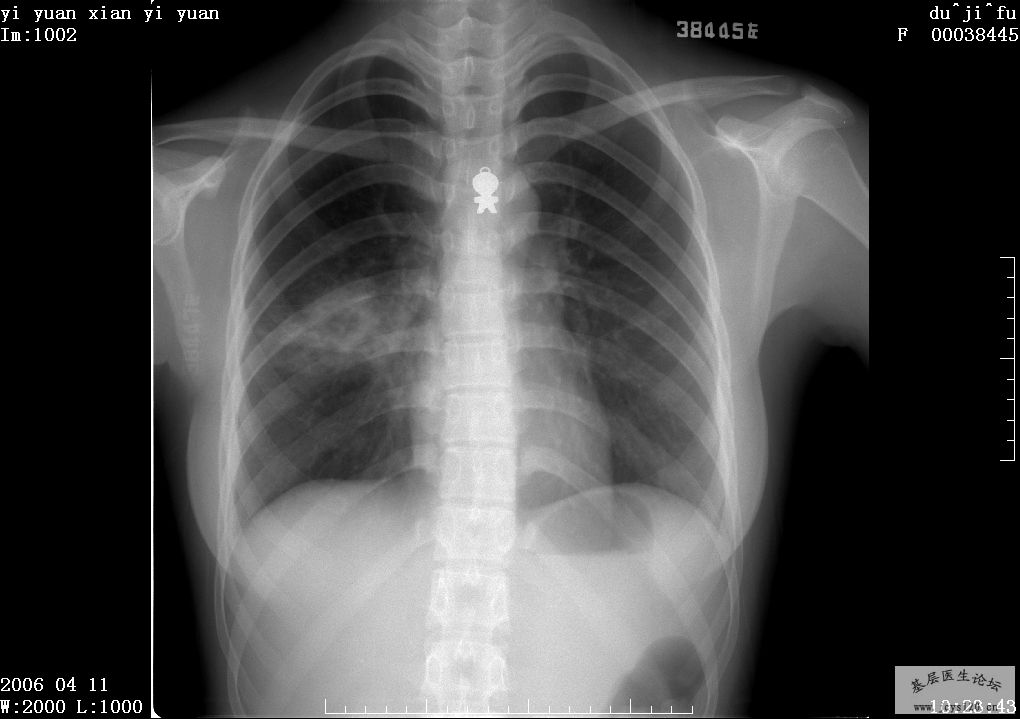

同行帮给看一下这个造影,需要怎么治疗比较理想

- 版主: eve592370698 版规概要: 1.求助帖,请交代患者的性别、年龄、现病史及检查目的这3个资料,最好提供既往史、家族史、摄片时身上有无杂物(这个真的很让人头疼,因为胸片有些病人身上的杂物是显影的,对正常诊断有很大的干扰作用); 2.汇总贴,本类帖子往往资料并非楼主一人提供,而是大家每个人贡献一点汇聚到一起,所以请勿灌水,如对某个楼层的资料有异议请尽量使用点评或者评分功能; 3.水贴,再次说一下,考虑到本版人气不太高,灌水我可能不会惩罚,但是请允许我对水帖进行删除、编辑、转移, 4.如还有疑问,请【点击这里】